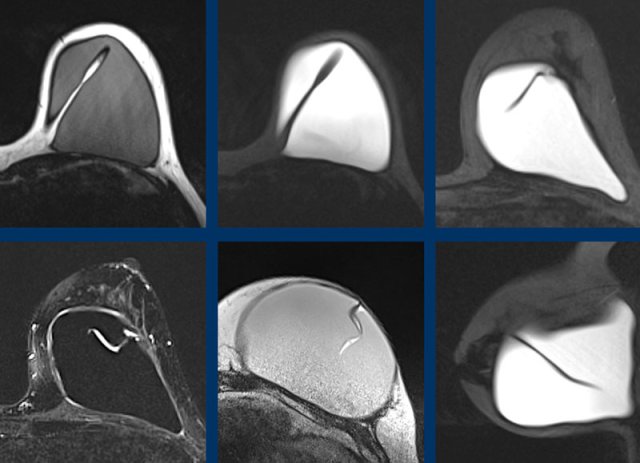

Intracapsular rupture

When there is silicone within a fold, then it is a sign of intracapsular rupture.

The images show:

- Teardrop sign: where the walls touch each other (1).

- Keyhole or Noose sign: different shapes, the walls do not touch each other (2-3).

Here another example of the different presentations of intracapsular rupture with silicone outside the envelope, but within the capsule.

- subcapsular line (yellow arrow)

- nose sign (blue arrow)

- teardrop sign (red arrow)

Linguine sign

This is the most reliable sign of intracapsular rupture.

The curvilinear lines which are formed by the ruptured envelope resemble Linguine pasta.